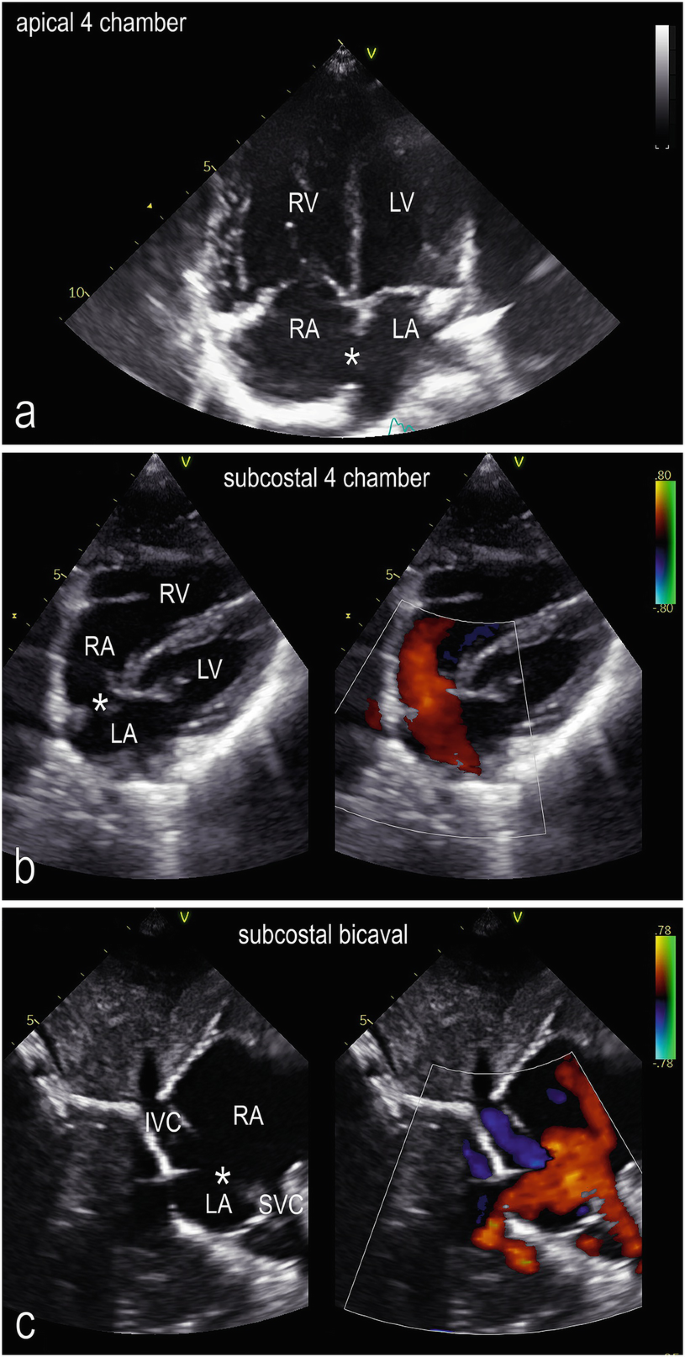

ostium secundum

» Ostium secundum asd (98) 사진

Ostium secundum asd (98) 사진